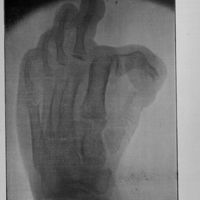

0176 - Page 148 - Travaux originaux. Deuxième partie. IV. Travaux de pathologie chirurgicale spéciale. Chirurgie des membres. Anomalie congénitale du gros orteil par implantation latérale ; reconstitution fonctionnelle intégrale par reposition sanglante (Planche 11 et 11 bis) / Rupture sous-cutanée complète du tendon d'Achille0176 - Page 148 - Travaux originaux. Deuxième partie. IV. Travaux de pathologie chirurgicale spéciale. Chirurgie des membres. Anomalie congénitale du gros orteil par implantation latérale ; reconstitution fonctionnelle intégrale par reposition sanglante (Planche 11 et 11 bis) / Rupture sous-cutanée complète du tendon d'Achille

0177 - Planche XI - [Planches]0177 - Planche XI - [Planches]